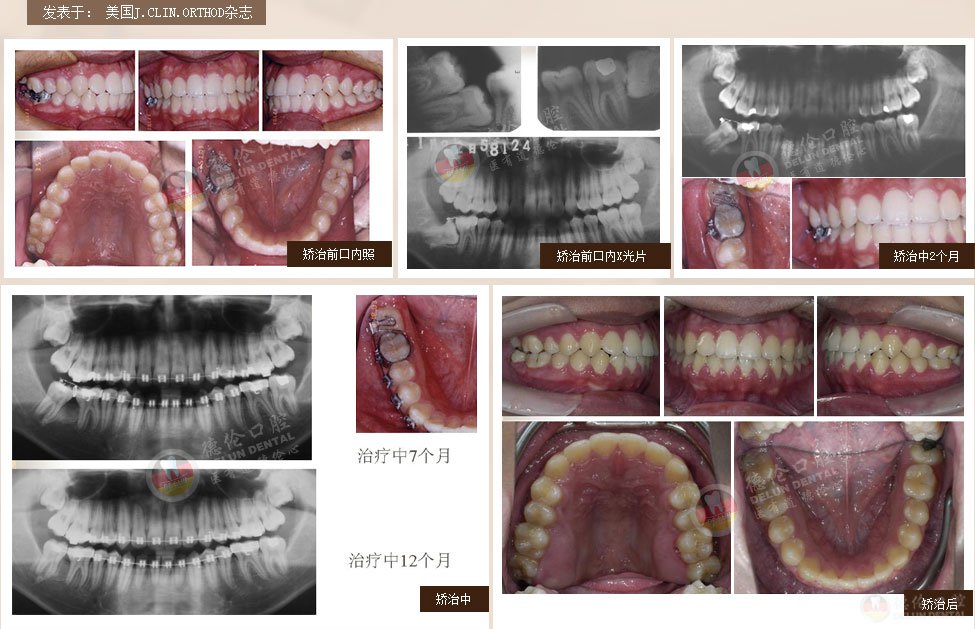

案例1:男 17岁

牙齿症状:下颌右侧第二、第三磨牙水平阻生,下颌左侧第三磨牙水平阻生

矫治方法:下颌拔除两颗第三磨牙(智慧齿)